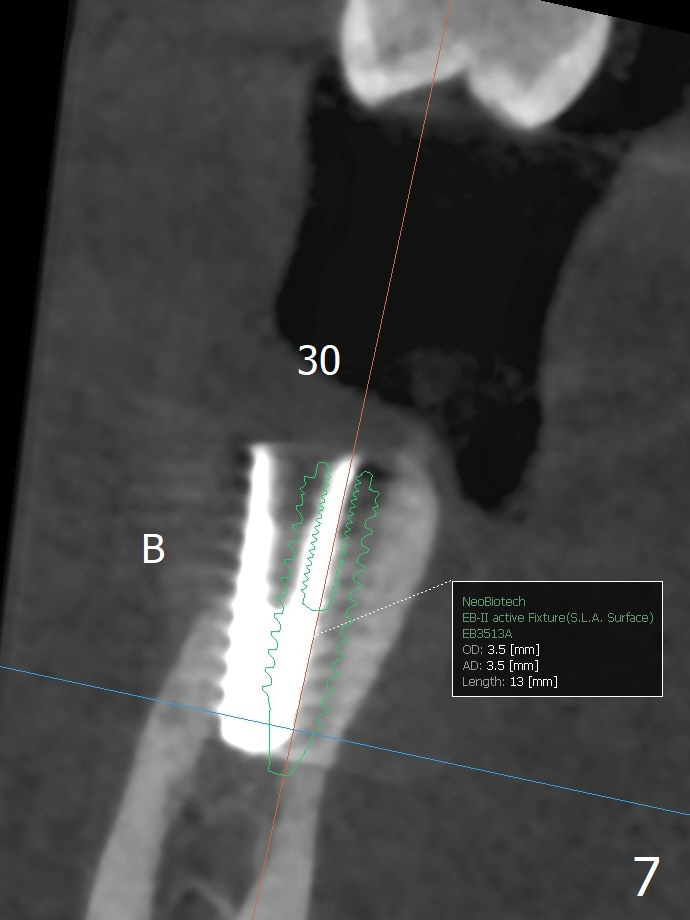

The implant at #30 was also buccally placed (Fig.6,7) and should be corrected in the same manner (Fig.7 green). Due to the bone being harder in the molar region, a smaller and shorter implant (4x11 mm vs. 5x13 mm) shifts slightly buccally while being placed (Fig.8,9). Since primary stability is lower (<20 Ncm vs. 35 Ncm associated with the implant #29), an abutment is not placed, which may be favorable to healing, but it is difficult to achieve primary closure. After bone graft (Fig.9 *) and 2 layers of PRF, Cytoplast is placed. Cytoplast appears to be exposed buccally (Fig.10 <) and occlusally (Fig.11 ^) asymptomatic 9 days postop. Exposure of Cytoplast is more distinct without sign of infection 15 days postop (Fig.12). The patient returns with chief complaint of "foul smell" 7 weeks postop (coronavirus lockdown). Although the Cytoplast exposes more (Fig.13 (* exposed; @ unexposed)), the underlying gingiva remains healthy (Fig.14). While the bone height decreases at #29, the bone density at #30 increases 4.5 months postop (Fig.15). The gingiva heals. The implant at #30 is uncovered 6 months postop. The lingual plate has to be removed for the uncover, while the coronal end of the buccal one is missing. No bone graft is added. When the 4.5x4 mm healing abutment is removed 6.5 months postop, the buccal plate looks concave at #30 (Fig.16' *). The buccal plate looks thin at #29 with a cotton roll placed buccally (Fig.16 R). The lingual plate at #29 is coronal to the buccal one (Fig.17). The buccal gingiva at #29 is quite long (Fig.18). The coronal buccal plate appears to be missing (Fig.19 >), which will be watched. A 4.5x7.5(4) mm cemented abutment is torqued (Fig.20).